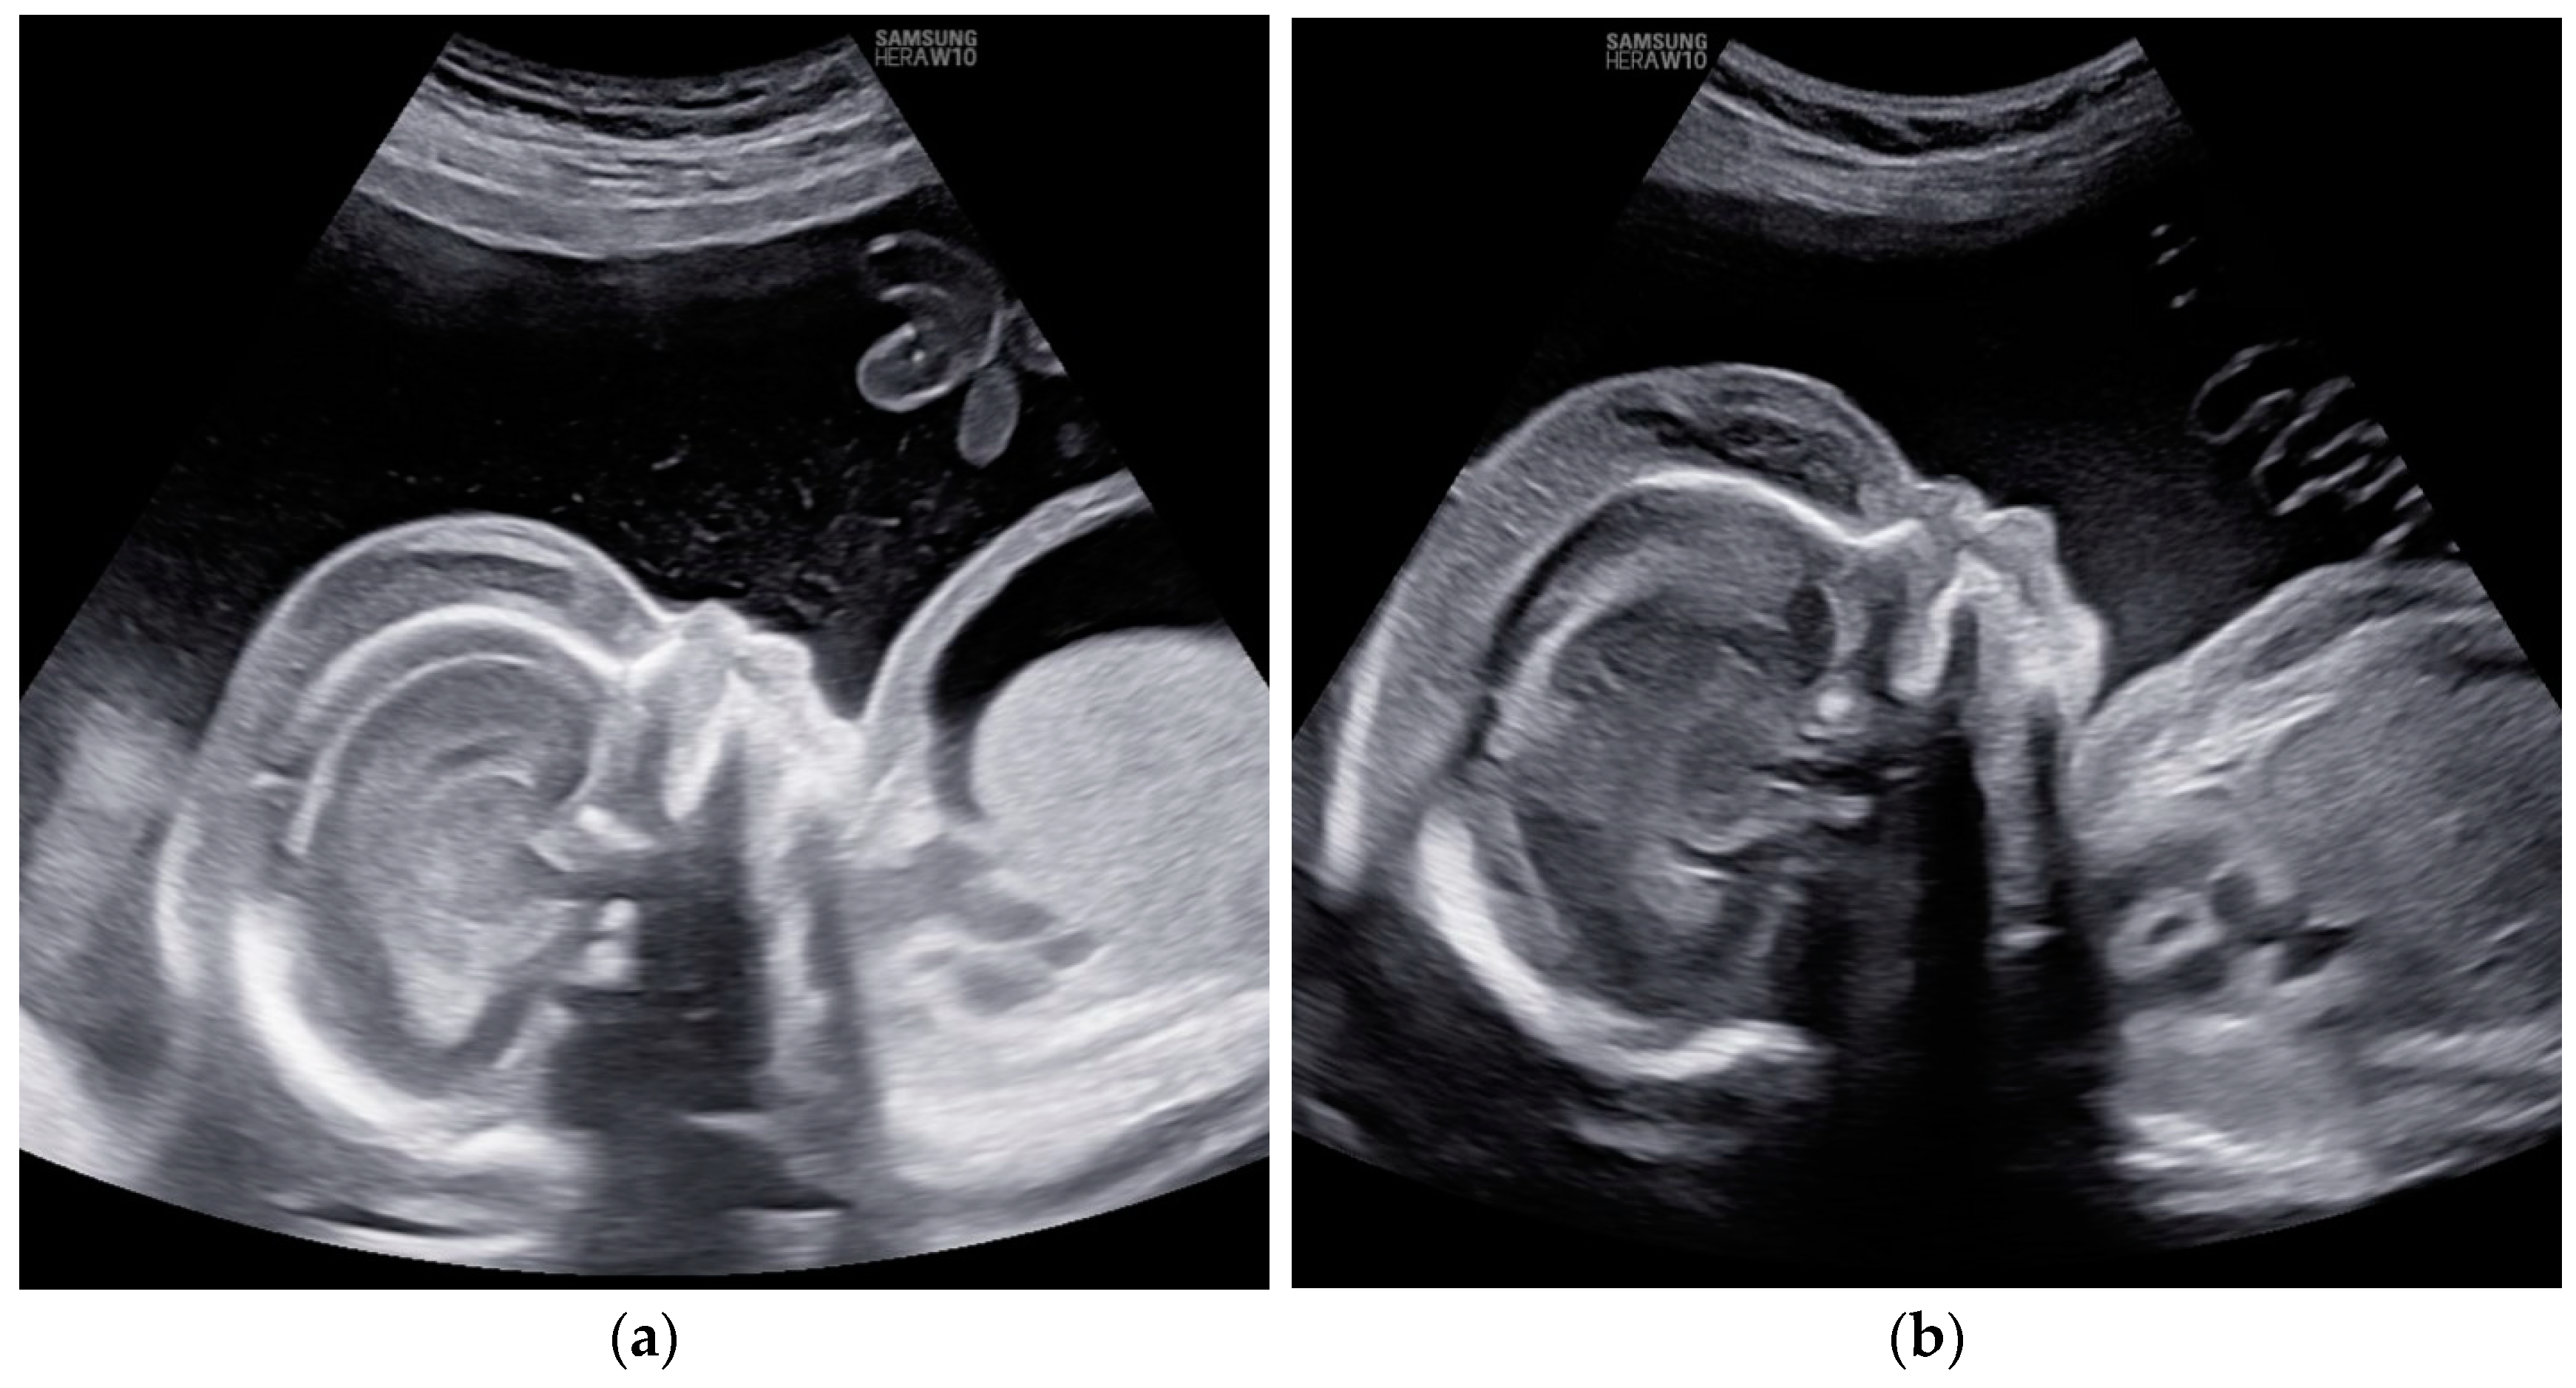

Despite a slight improvement in Doppler findings, no resolution of fetal hydrops was observed (Figure 2).

Figure 2. Case 4: Edema of fetal subcutaneous tissue; no signs of resolution of hydrops; (a) before first intrauterine transfusion, 20 weeks of gestational age; (b) after third intrauterine transfusion, 24 weeks of gestational age.